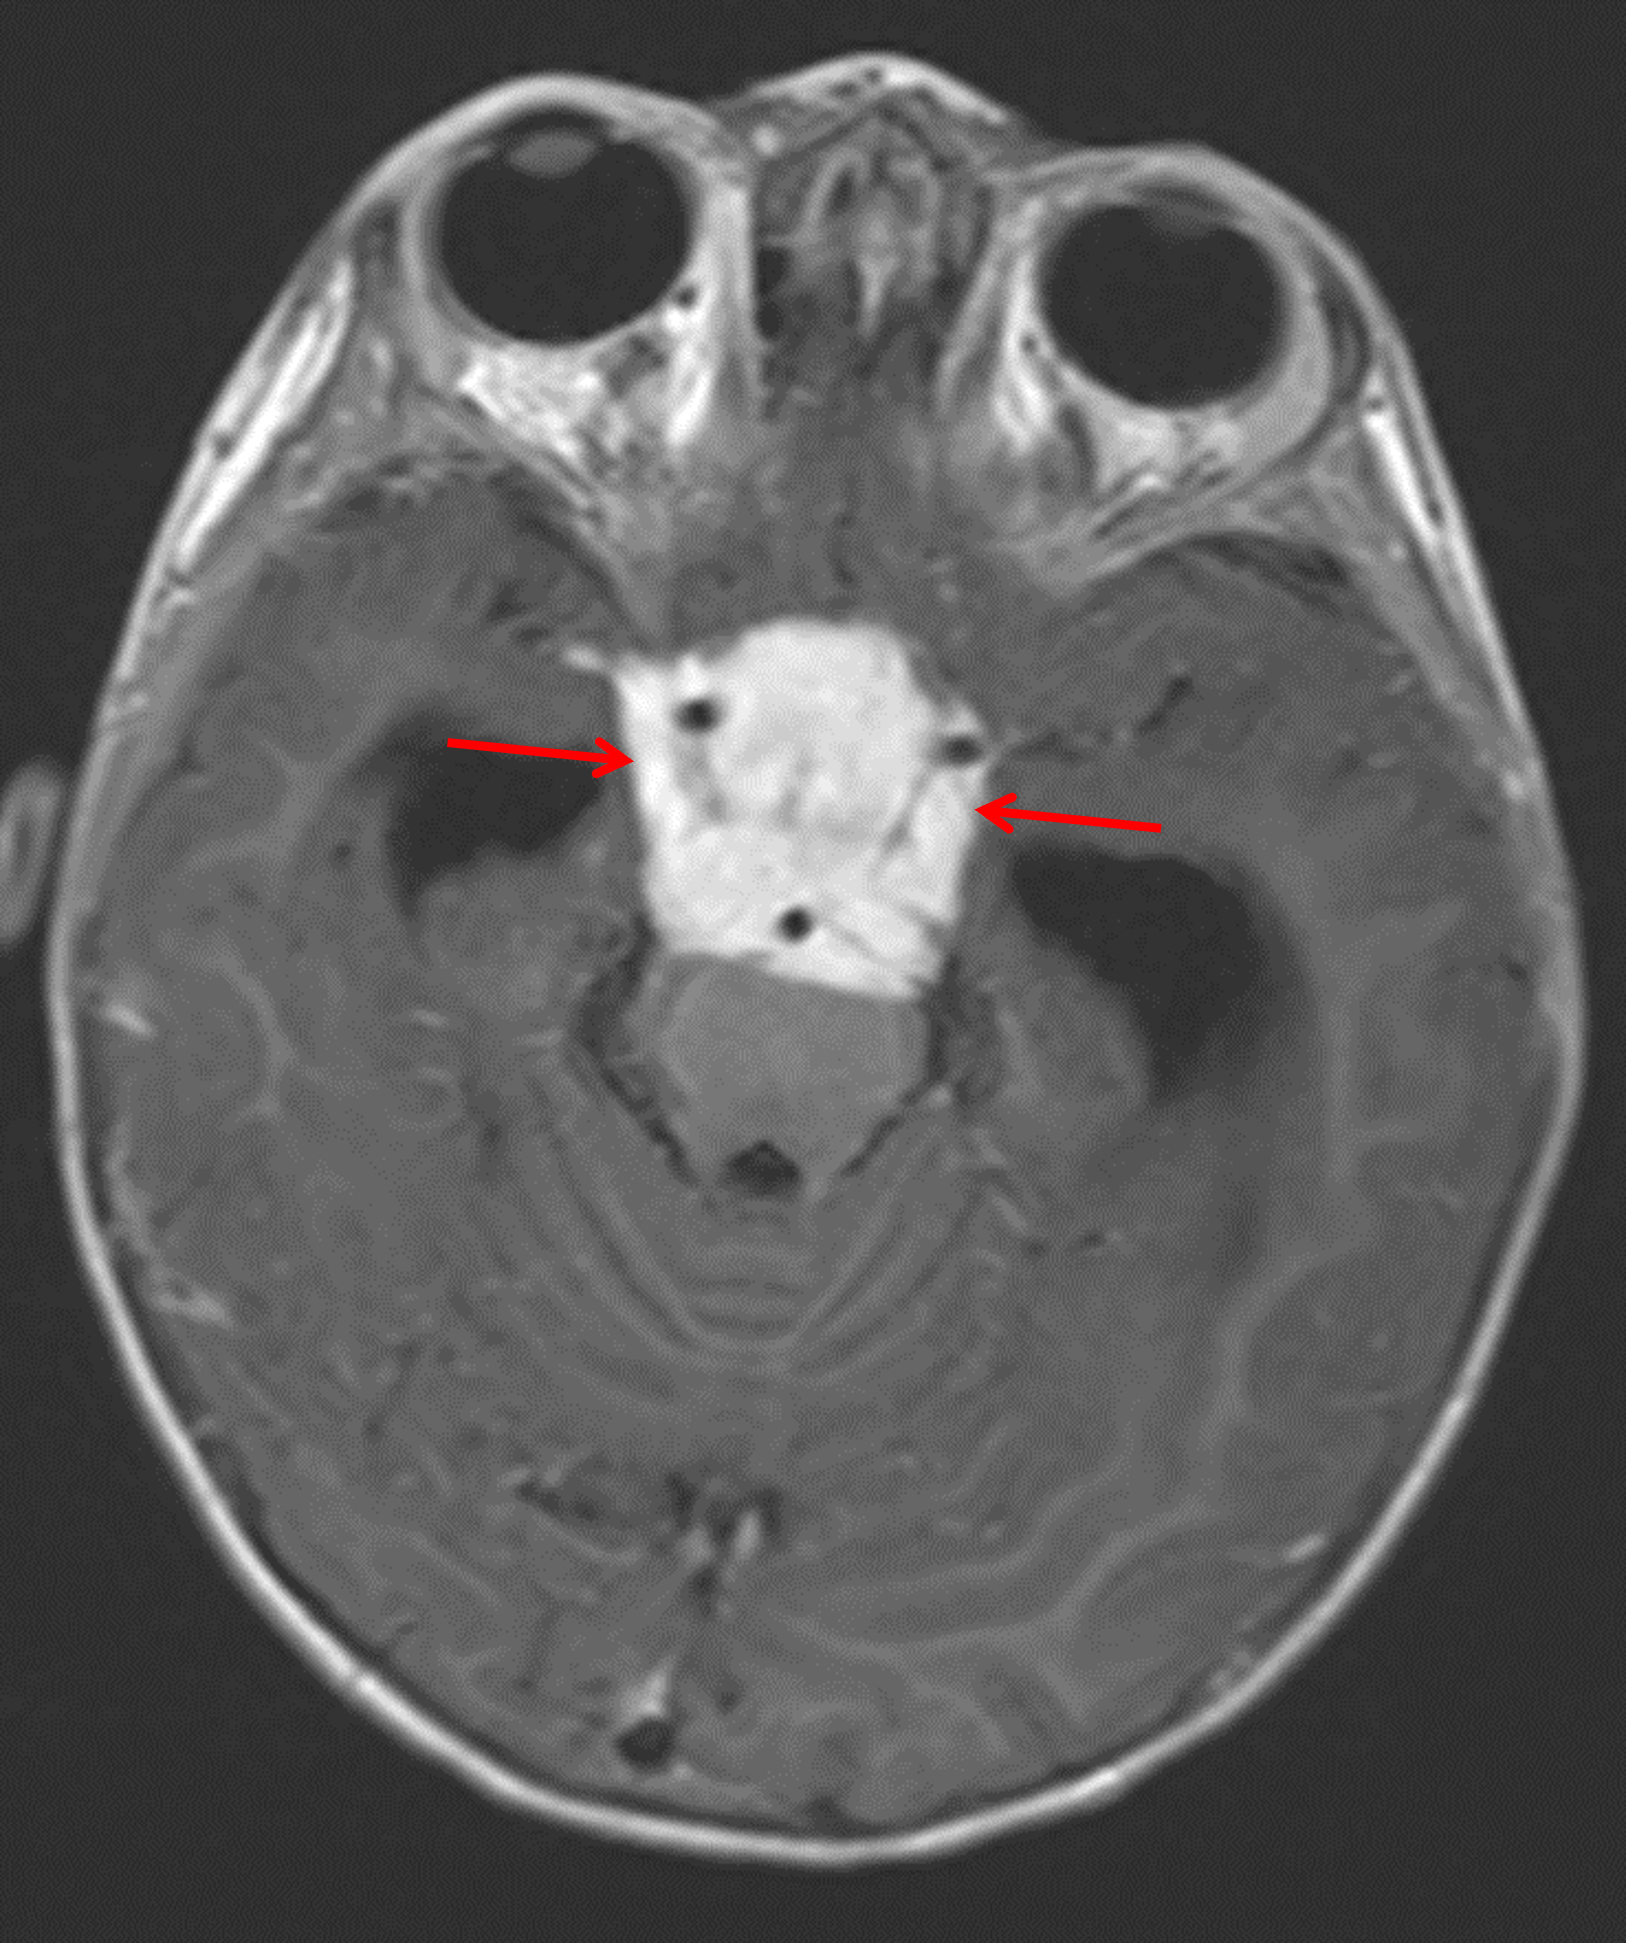

Age: 2

Sex: Female

Indication: Failure to thrive

CT (performed a few days after the MRI)

Pilomyxoid astrocytoma